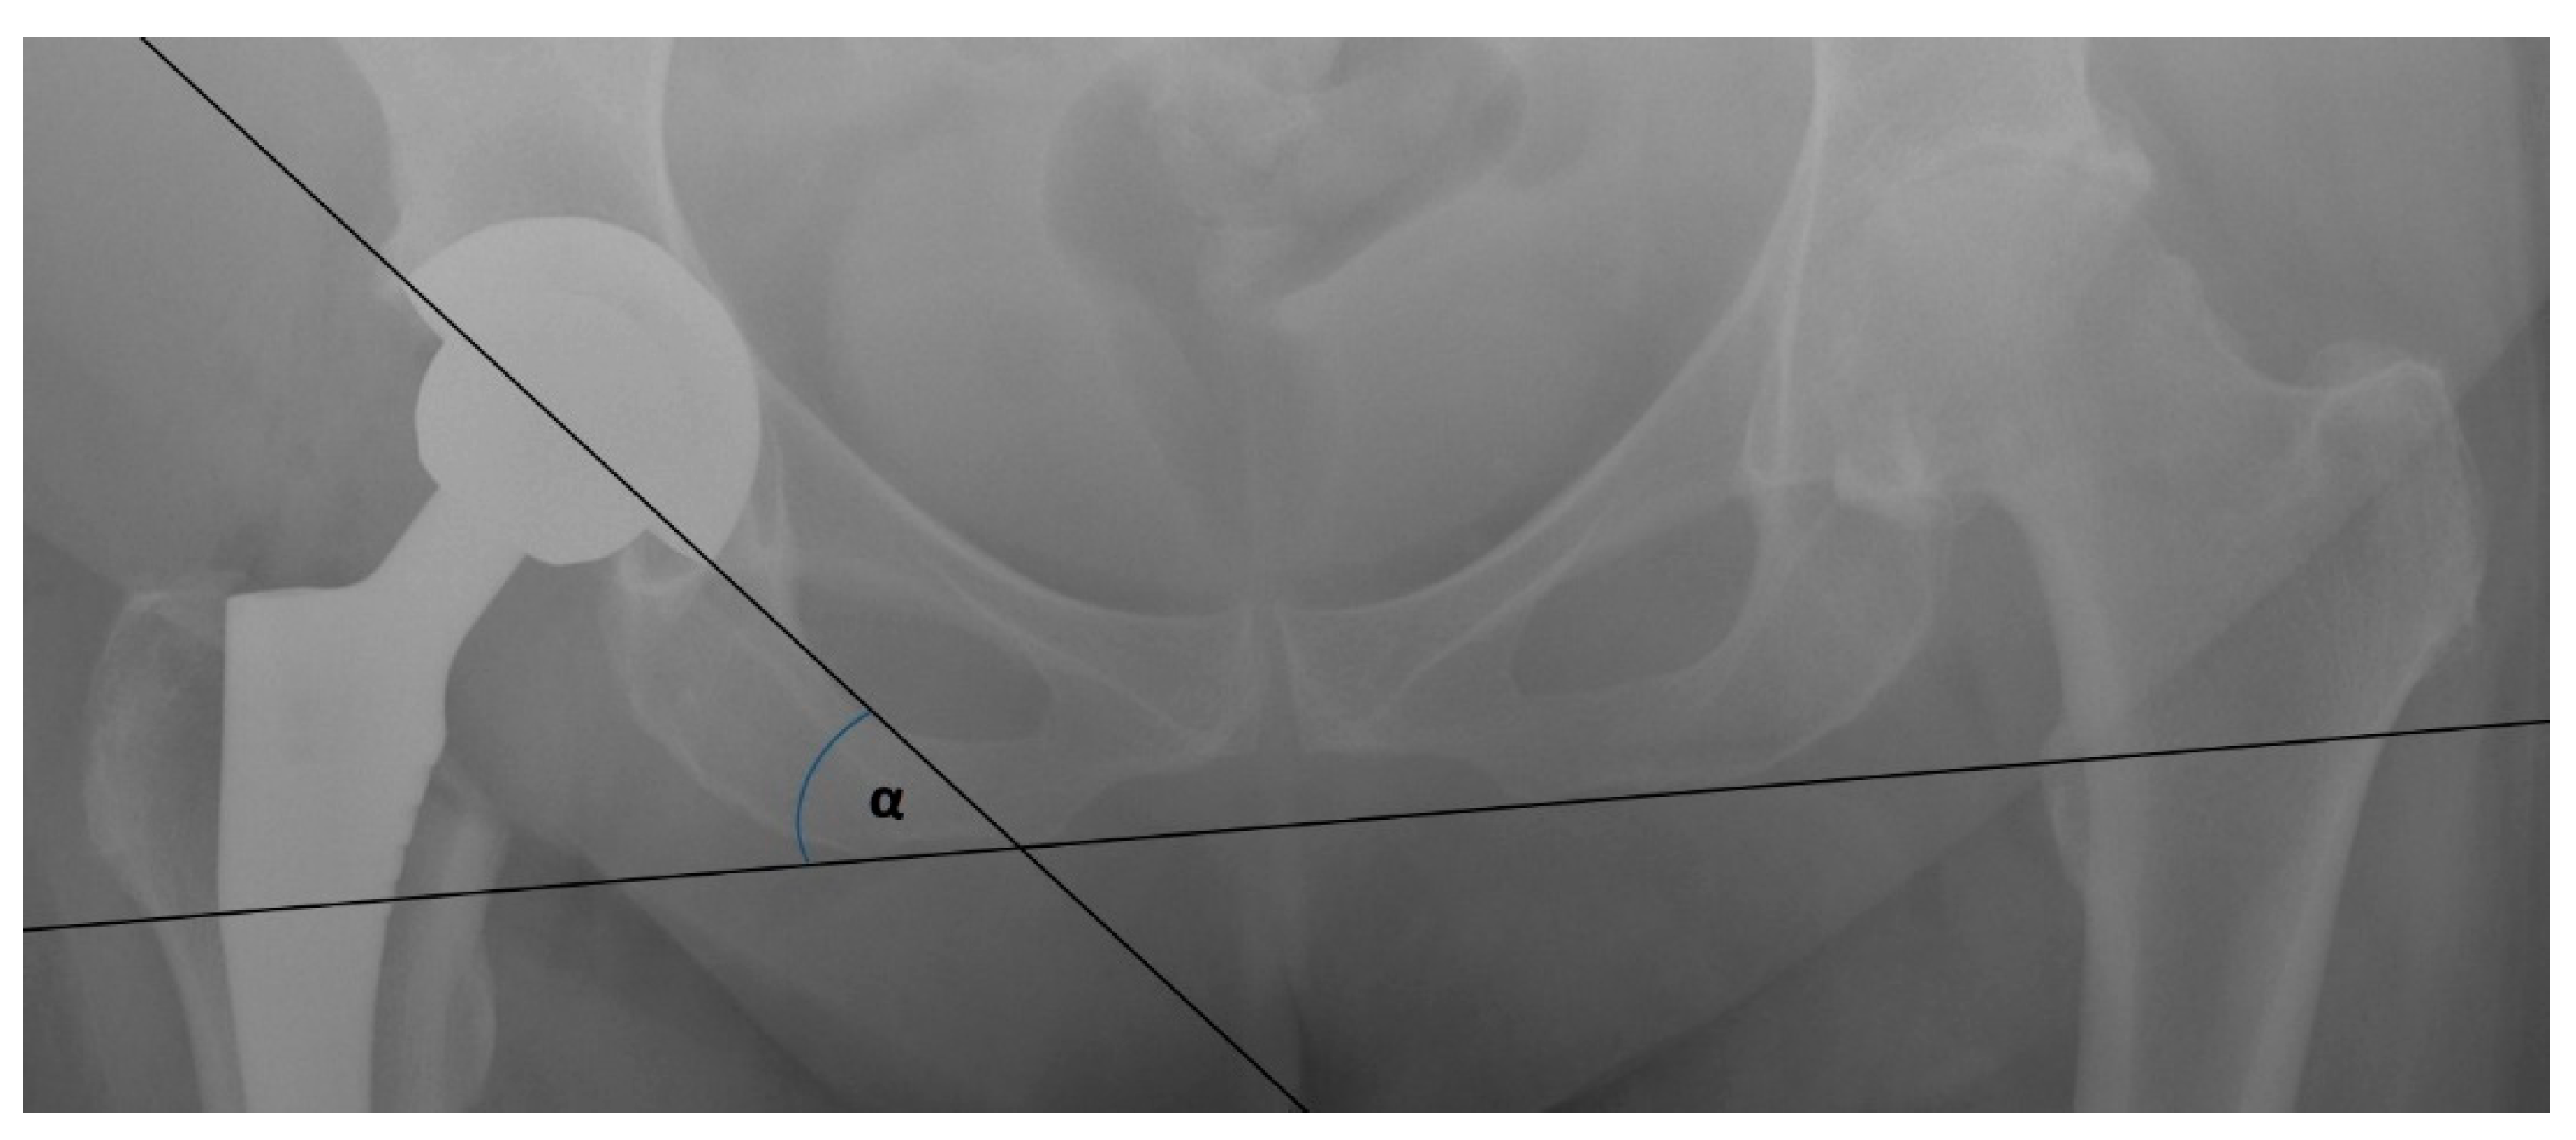

3.2. Femoral Stem Alignment

3.3. Mean Radiographic Cup Inclination

3.4. Mean Radiographic Cup Anteversion

3.5. Leg Length